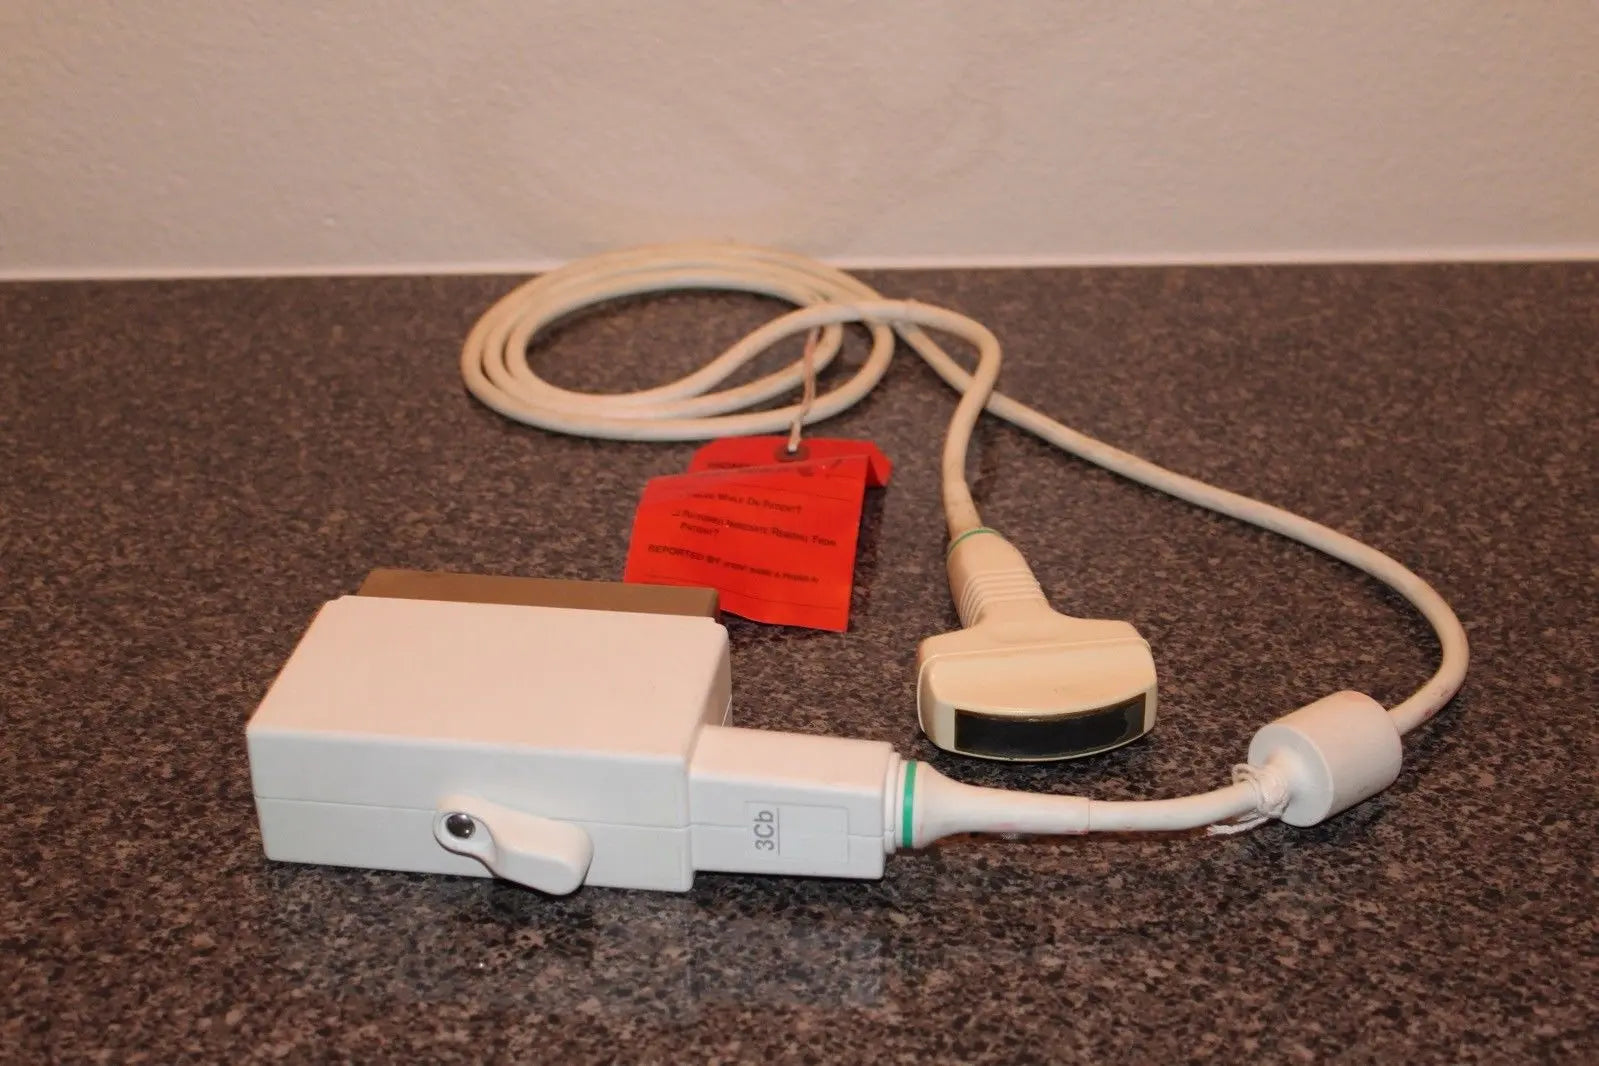

DIAGNOSTIC ULTRASOUND MACHINES FOR SALE

GE 3CRF Ultrasound Probe Transducer DOM 2011

Sale price$ 2,089.60